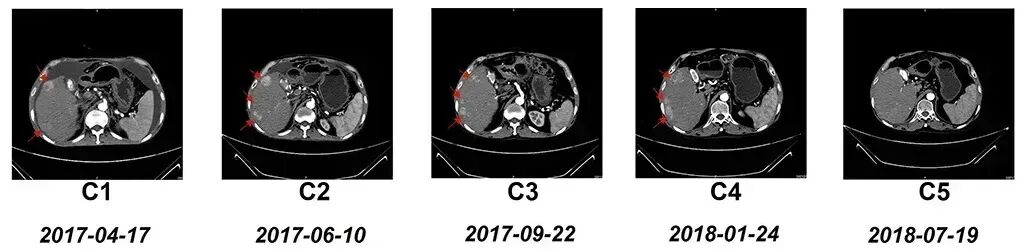

NK细胞作为人体免疫系统的重要防线,具有抗癌及抗病毒的双重功效,近年研究人员将其用于治疗慢性乙肝导致的肝细胞癌,并取得了令人赞叹的疗效。《肿瘤靶点和治疗》杂志就曾报道过一个“晚期弥漫性肝细胞癌患者经NK细胞治疗后,胸/腹水及肿瘤病灶显著改善”的案例。

该患者是一位59岁的IV期弥漫性肝细胞癌(HCC)男性患者,有慢性乙肝病史,确诊肝癌后,曾接受过经导管动脉化疗栓塞术(TACE)、腹膜穿刺手术、顺铂等治疗,但病情仍然继续进展,遂入组接受了17个疗程的NK细胞治疗。结果显示如下:

1、腹水及胸水明显减少:该患者在完成6个疗程的NK细胞治疗后,复查CT显示,腹水几乎完全消失(详见图B1~B5),胸腔积液也完全消失(详见图A1~A5)。

图片

▲图源“Dovepress”,版权归原作者所有,如无意中侵犯了知识产权,请联系我们删除

2、肿瘤体积缩小:该患者在完成全部17个疗程的NK细胞治疗后,复查CT显示,右肝叶多处肿瘤病灶出现显著缩小(详见下图)。